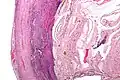

Pathology diagnosis of appendicitis can be made by detecting a neutrophilic infiltrate of the muscularis propria.

Micrograph of appendicitis and periappendicitis. H&E stain

Micrograph of appendicitis showing neutrophils in the muscularis propria. H&E stain

Acute suppurative appendicitis with perforation (at right). H&E stain